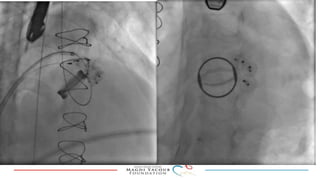

This document provides an overview of percutaneous prosthetic valve leakage (PVL) closure, including indications, approaches, techniques, and closure devices. It discusses that over 210,000 prosthetic valve surgeries are performed each year, with PVL occurring in some cases. While surgical closure has a high mortality rate, percutaneous closure has a procedural success rate of 86% and less complications. Indications for closure include symptomatic heart failure, hemolysis, rocking prosthesis, or leaks over 30% of the sewing ring. Techniques discussed include retrograde and transapical approaches using devices like the Amplatzer and Occlutech plugs. A team approach and techniques like sequential deployment are emphasized for